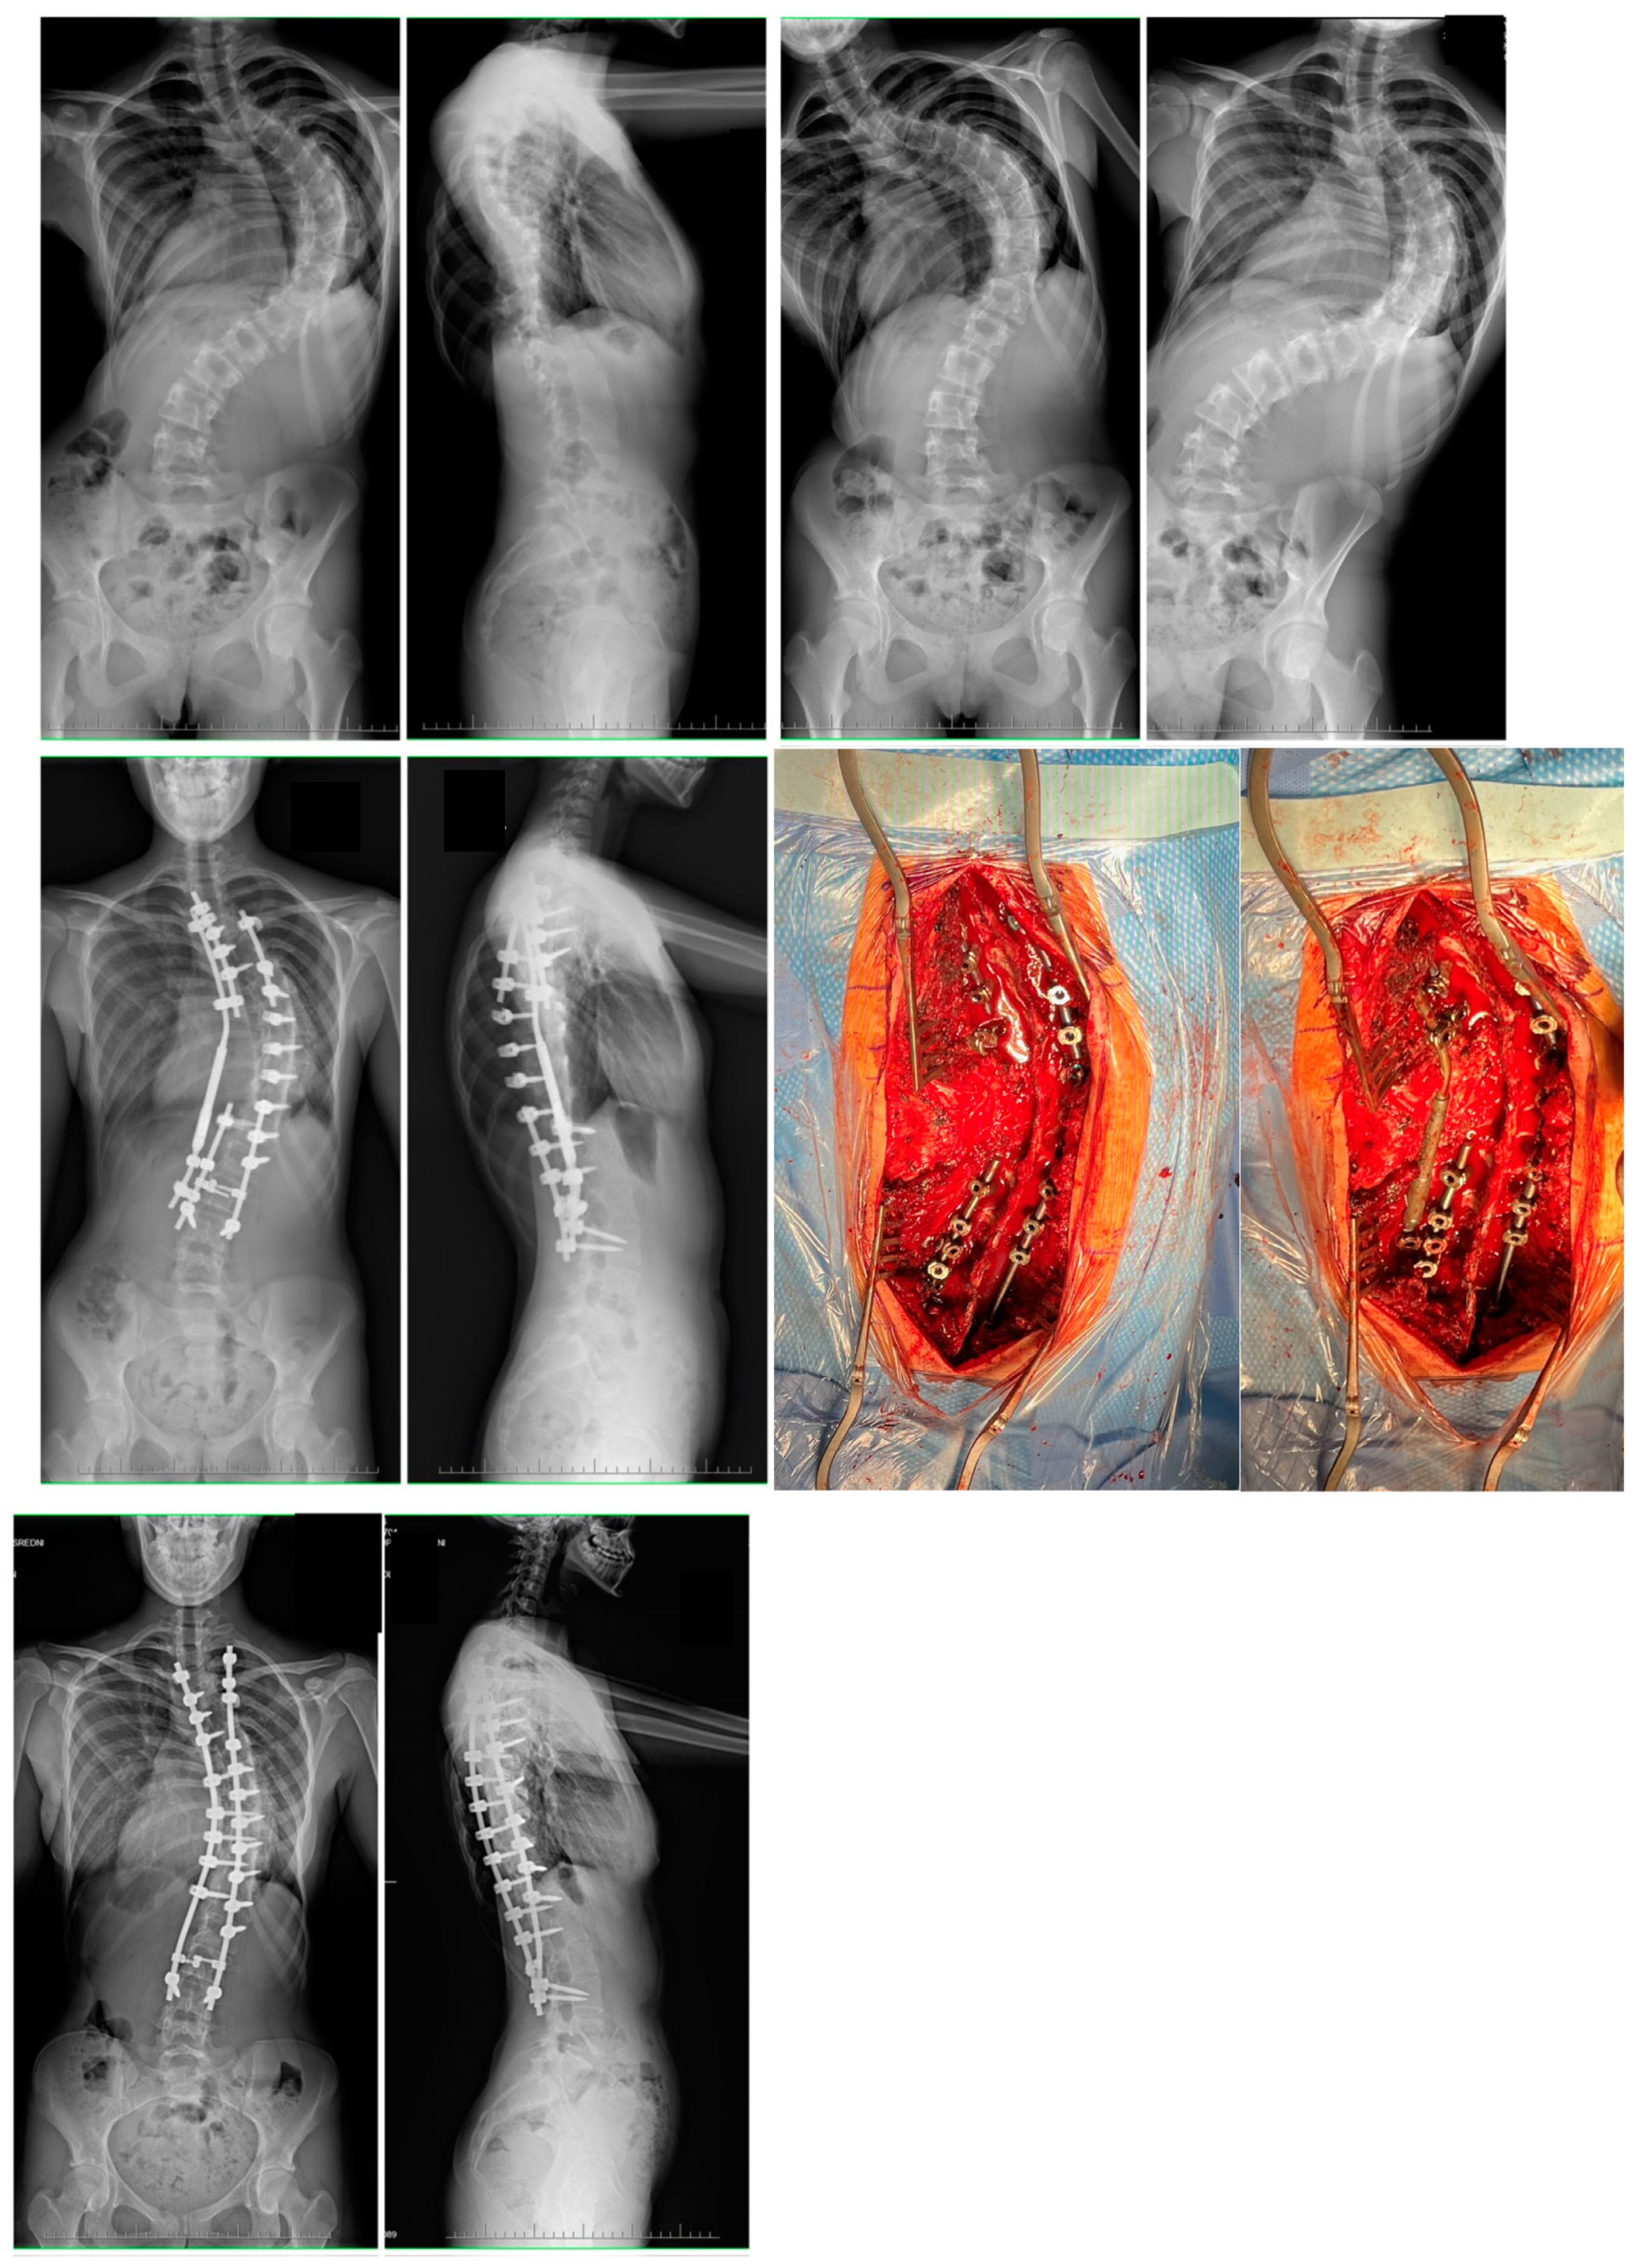

2.3. Surgical Technique

3.1. Clinical Characteristics and Radiographic Outcomes

3.2. Complications